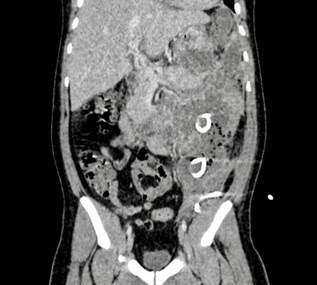

A new abdominal CT scan (Figure 1) showed pancreatic necrotic collections dependent on the tail, with central and left-sided abdominopelvic distribution, and these collections were in contact with the gastric wall.